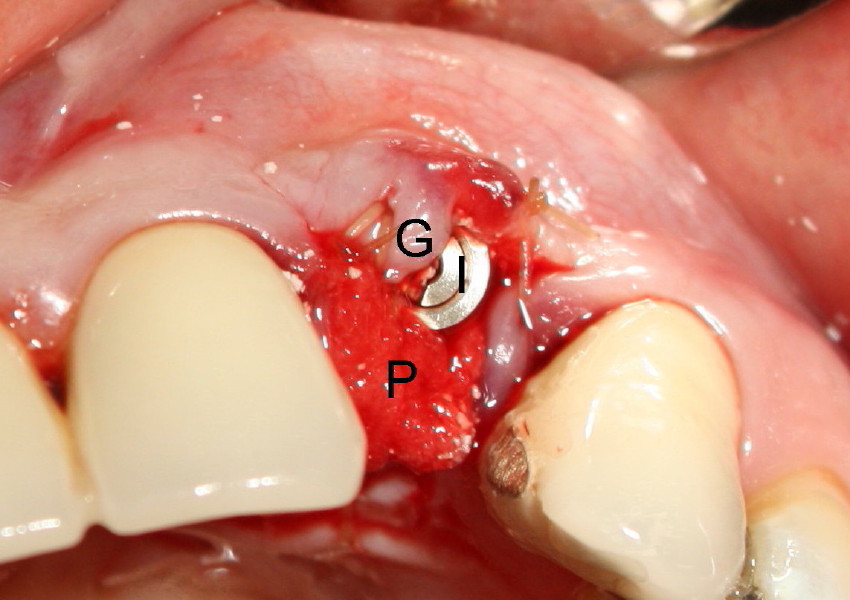

Fig.3 It turns out that the incision design is not helpful.  As bone is expanded with Tatum's D implant kit, osteotomy becomes more and more buccal.  After D1 implant (4x16 mm) is placed (I), there is extra gingiva (G) buccally, whereas lingual osteotomy is exposed.  Bone graft (Bicon Synthograft) and collagen plug (P) have to be used to close the wound, back to main text